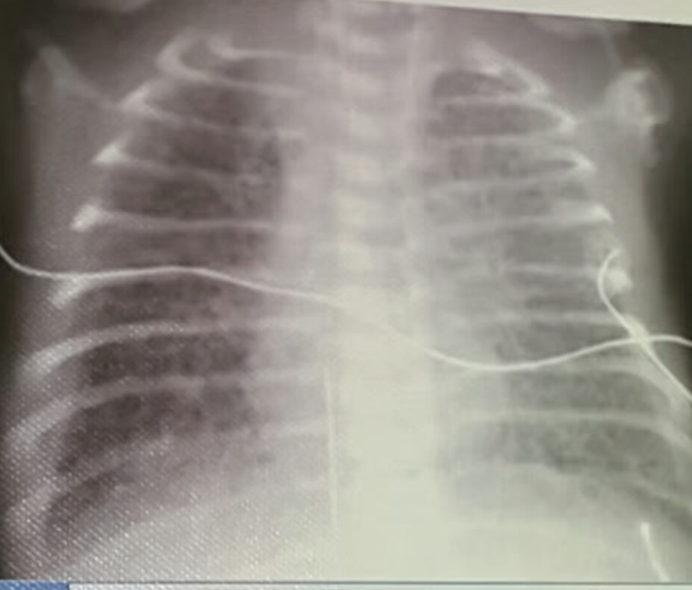

- Anterio-posterior [AP] chest radiograph shows multiple cystic lesions inâ (1 -the middle and lower zones of the left hemi-thorax with ill-defined left hemi diaphragm. There is mediastinal shift toward the right. These lesions are -bowel loops inside the left hemi-thorax. The film is over exposed (over .(penetration

- The diagnosis is Left Sided Congenital Diaphragmatic Hernia (CDH). This - (2 is called bockdalic CDH. CDH is usually in the left side (90 %). The defect is found in the posterio-lateral aspect of the diaphragm. CDH is associated with .lungs hypoplasia in the same side and to a lesser extent in the opposite side .This may be complicated by pulmonary hypertension and severe hypoxemia

- The treatment of CDH is immediate endo-tracheal incubation if it is - (3 diagnosed in-utero or if it is highly suspected after birth (with following symptoms and; respiratory distress (RD), cyanosis, asymmetrical chest movement, bowel sounds heard in the chest and scaphoid abdomen). After intubation, the patients is put on mechanical ventilator and the pulmonary hypertension [PH] is controlled and hypoxemia is reversed. PH and severe hypoxemia may require inhaled Nitric Oxide [iNO], High frequency Oscillatory Ventilation [HFOV] and Exogenous Surfactant administration through endotracheal tube [ETT]. After the stabilization of the arterial blood gases the patient is taken to suture the defect. If the defect is large, a mesh,[ABGs] device may be used. The most important differential diagnosis is Cystic .Adenomatoid Malformation [CAM]